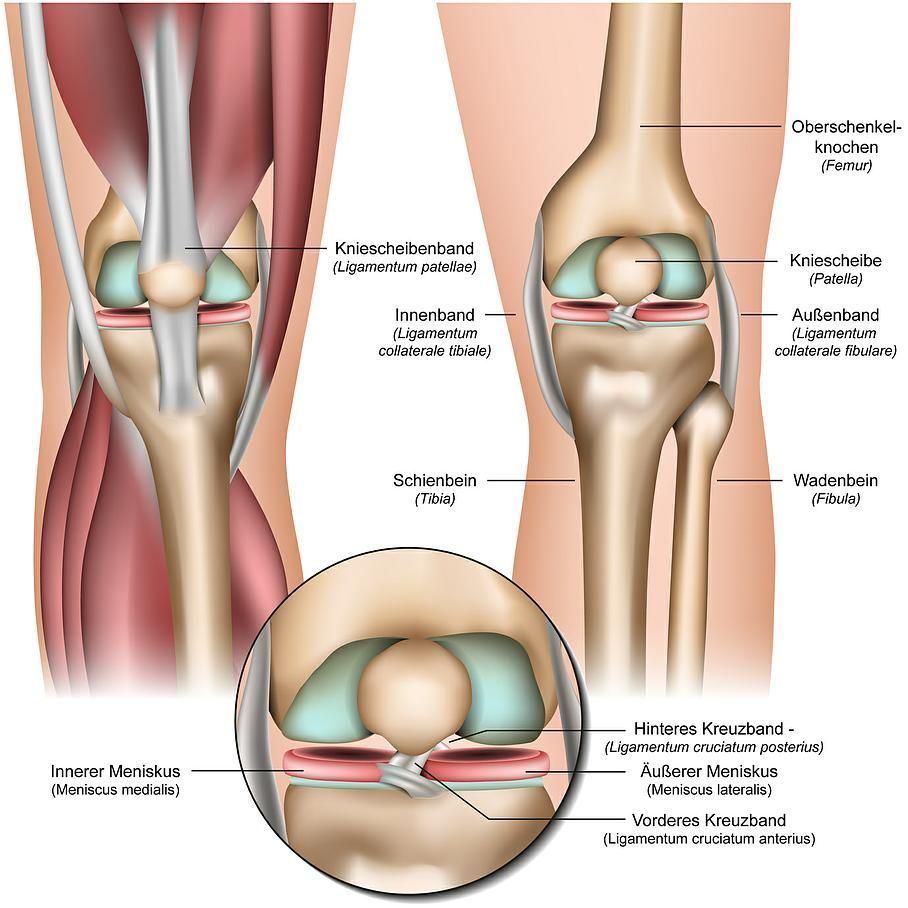

Pathologies du genou:

Lésion ligamentaire du genou:

Le genou est stabilisé par quatre ligaments, les ligaments latéraux (médial et latéral) et les ligaments croisés (antérieur et postérieur).

Les lésions des ménisques:

Il existe deux ménisques dans le genou, le ménisque externe et interne, qui est du cartilage fibreux. Ils agissent comme amortisseur entre le fémur et le tibia, afin de protéger le cartilage de l’articulation du genou. Ils ont aussi un rôle dans la congruence articulaire et sont donc indispensables au bon fonctionnement du genou.

Instabilité de la rotule:

La rotule est l’os situé en avant du genou et fait partie de l’appareil extenseur du genou. La luxation de la rotule se manifeste par la perte de contact et un déplacement vers l’extérieur par rapport au fémur. Cette luxation peut être post-traumatique ou spontanée et plus ou moins récidivante.

L’arthrose du genou ou gonarthrose:

Les fractures de l’articulation du genou: